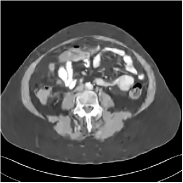

We used Mayo Clinics dataset established for “the 2016 NIH-AAPM-Mayo Clinic Low Dose CT Grand Challenge” [53] in our experiments. We randomly selected 520 slices from data (of 3 mm thickness) for six out of ten patients, from which 500 slices were used for training and 20 slices were used for validation. We extracted 18 regular-dose CT images from the 500 training slices to pre-train a union of five sparsifying transforms used for the ULTRA regularizer. We tested on 20 slices that were randomly extracted from the remaining four patients’ data. We simulated low-dose CT sinograms 𝐲𝐲\mathbf{y} from the provided regular-dose images 𝐱superscript𝐱\mathbf{x}^{*} using the Poisson-Gaussian noise model [54, 14]:

yi=log(I01max(Poisson{I0e[𝐀𝐱]i}+𝒩{0,σ2},ϵ)),subscript𝑦𝑖superscriptsubscript𝐼01Poissonsubscript𝐼0superscript𝑒subscriptdelimited-[]superscript𝐀𝐱𝑖𝒩0superscript𝜎2italic-ϵ\centering y_{i}=-\log\left(I_{0}^{-1}\max\big{(}\textup{Poisson}\{I_{0}e^{-[\mathbf{A}\mathbf{x}^{*}]_{i}}\}+\mathcal{N}\{0,\,\sigma^{2}\},\epsilon\big{)}\right),\@add@centering

where the number of incident photons per ray is I0=104subscript𝐼0superscript104I_{0}=10^{4}, the Gaussian noise variance is σ2=25superscript𝜎225\sigma^{2}=25, and ϵitalic-ϵ\epsilon is a small positive number to avoid negative measurement data when taking the logarithm. We used the Michigan Image Reconstruction Toolbox111Jeffrey A Fessler, available at http://web.eecs.umich.edu/~fessler/irt/irt. to construct fan-beam CT geometry with 736 detectors ×\times 1152 regularly spaced projection views, and a no-scatter monoenergetic source. The width of each detector column is 1.2858 mm, the source to detector distance is 1085.6 mm, and the source to rotation center distance is 595 mm. We reconstruct images of size 512×512512512512\times 512 with the pixel size being 0.69 mm ×\times 0.69 mm.